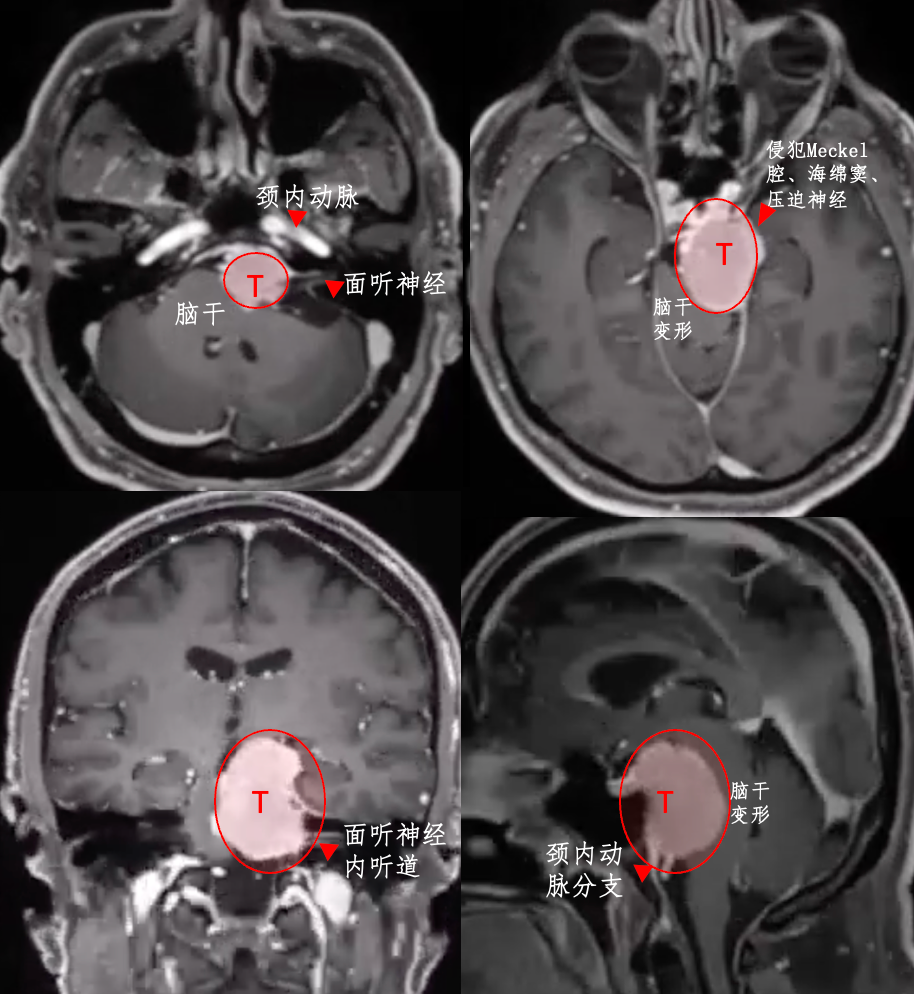

54岁男性Bruno,也是岩斜区脑膜瘤,但是他就没那么幸运了。左侧脸部如刀割般疼痛,甚至还出现吞咽困难,无法进食、难以入眠、无法工作……

为什么他的症状如此严重?

2014年,查出岩斜区脑膜瘤,考虑到这是个良性肿瘤,且手术治疗有风险,他选择了保守观察。然而,6年时间,肿瘤持续增长,压迫脑干,症状不断恶化。

福教授采用开颅手术,术前通过线圈在咽升动脉处进行栓塞,可以显著减少术中出血。在切除肿瘤过程中,使用CUSA刀对肿瘤逐渐减瘤。术后MRI显示肿瘤几乎完全切除,脑干受压解除。